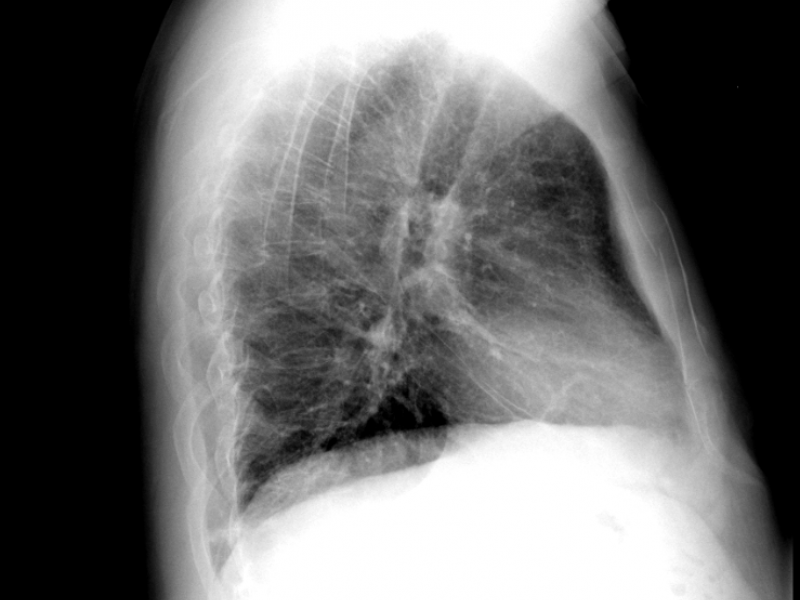

A 59 yo M presents to the ED complaining of chest pain